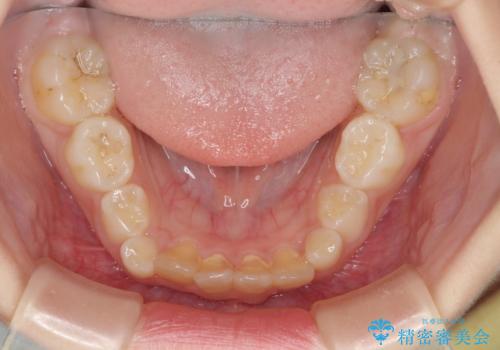

- 前歯の叢生を気にして来院された、小学校3年生女児の患者様です。

身長がやや低く、乳歯から永久歯への交換が少し遅い印象があったので、ワイヤー装置による1期矯正治療ではなく、乳歯も積極的に動かすことのできるインビザライン・ファーストにて治療を行うこととしました。

上顎前歯に過剰歯があったため、まずはその歯を抜歯し、傷が治癒したタイミングでインビザラインを発注することとしました。